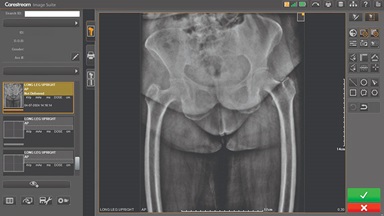

CARESTREAM Image Suite V4 MR11 has set a new standard for workflow efficiency, offering a robust set of features and functionalities to enhance clinical confidence in healthcare professionals. Using an auto-generated companion image from a single exposure, leverage a range of image processing options to increase diagnostic accuracy and enhance patient care.

Carestream Introduces New Software Update to Boost Diagnostic Accuracy

Carestream today announced the latest update to its Image Suite V4 Software, MR 11: a series of enhancements to help improve customer confidence and increase diagnostic accuracy [...]